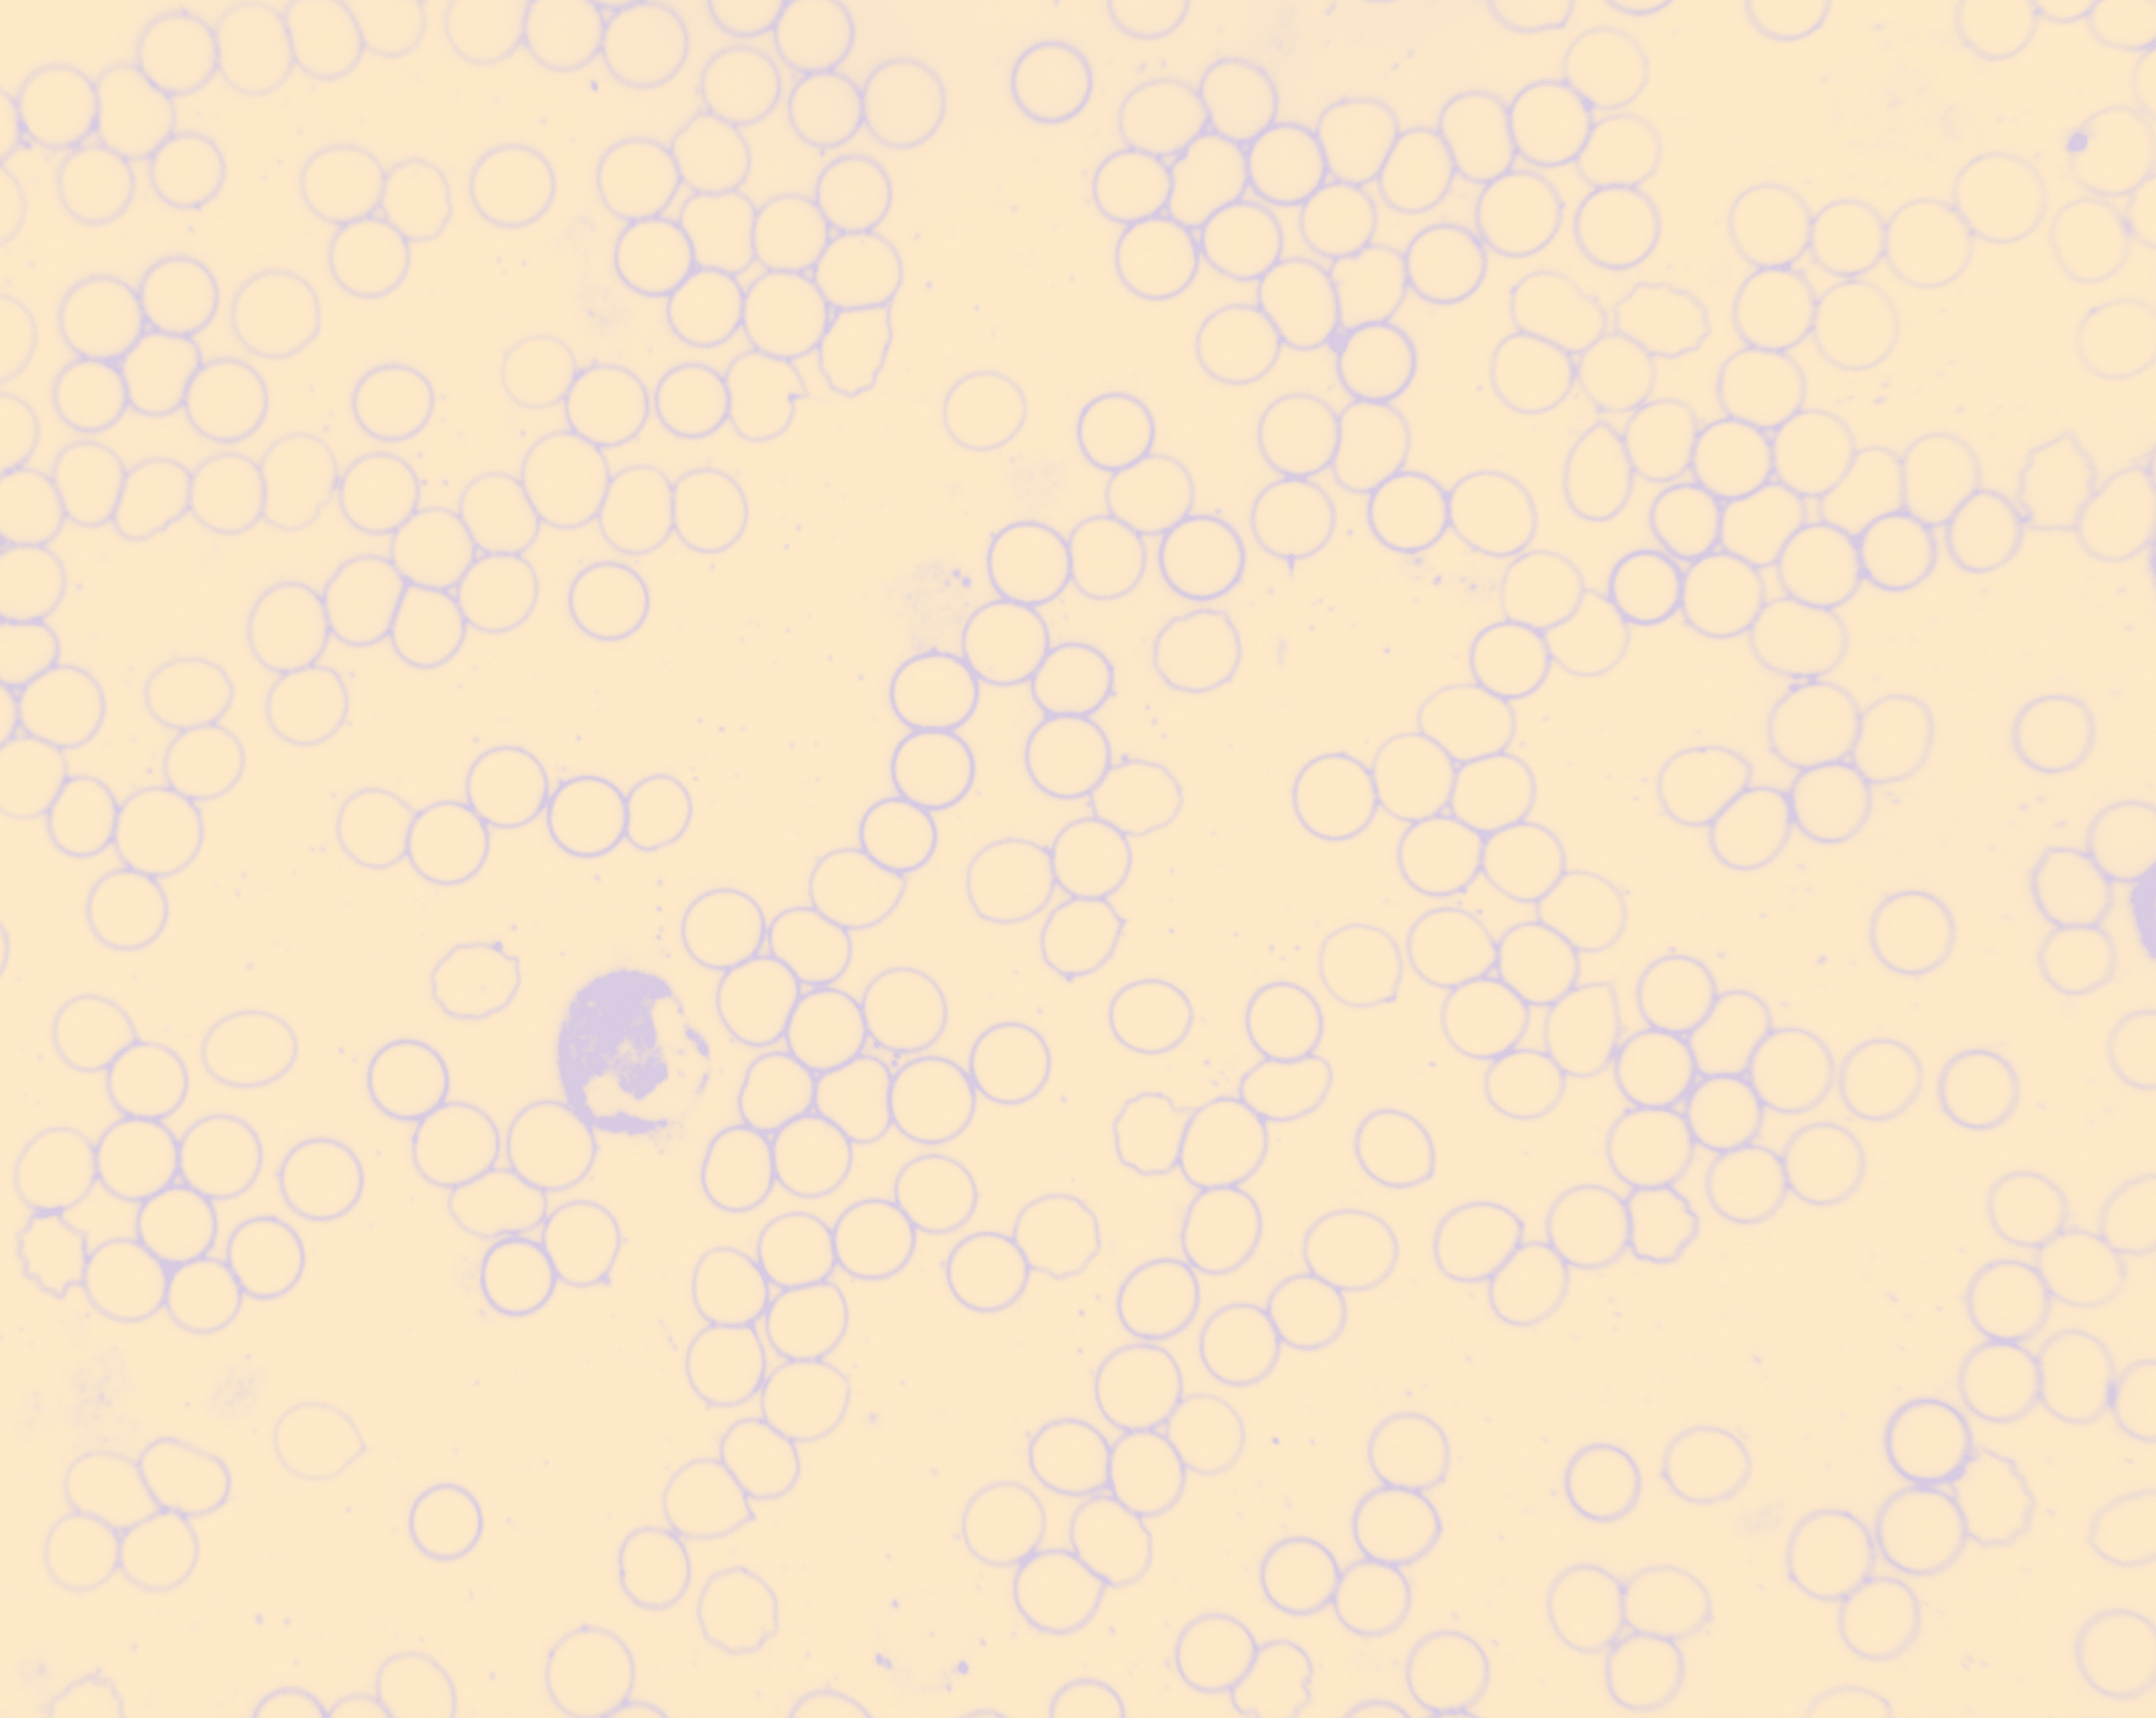

Diagnostisch arbeite ich dabei vor allem mit der Vitalblutanalyse nach Professor Doktor Günther Enderlein.Hierbei wird ein Tropfen Kapillarblut aus der Fingerkuppe unter dem Dunkelfeldmikroskop betrachtet, woraus sich zahlreiche Schlüsse auf die immunologische Situation, Allergieneigung, toxische und mikrobiologische Belastungen des Körpers und Fehlfunktionen einzelner Organe ziehen lassen.

Sie können diese Untersuchung am Bildschirm mitverfolgen. Anhand dieser Informationen und eventuell auch weiterer Untersuchungsergebnisse erstelle ich dann Ihren individuellen Therapieplan.